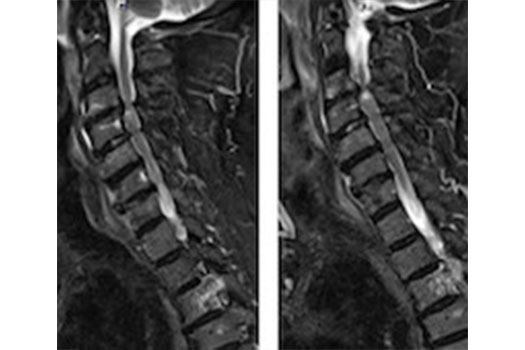

Myélopathie Cervicale